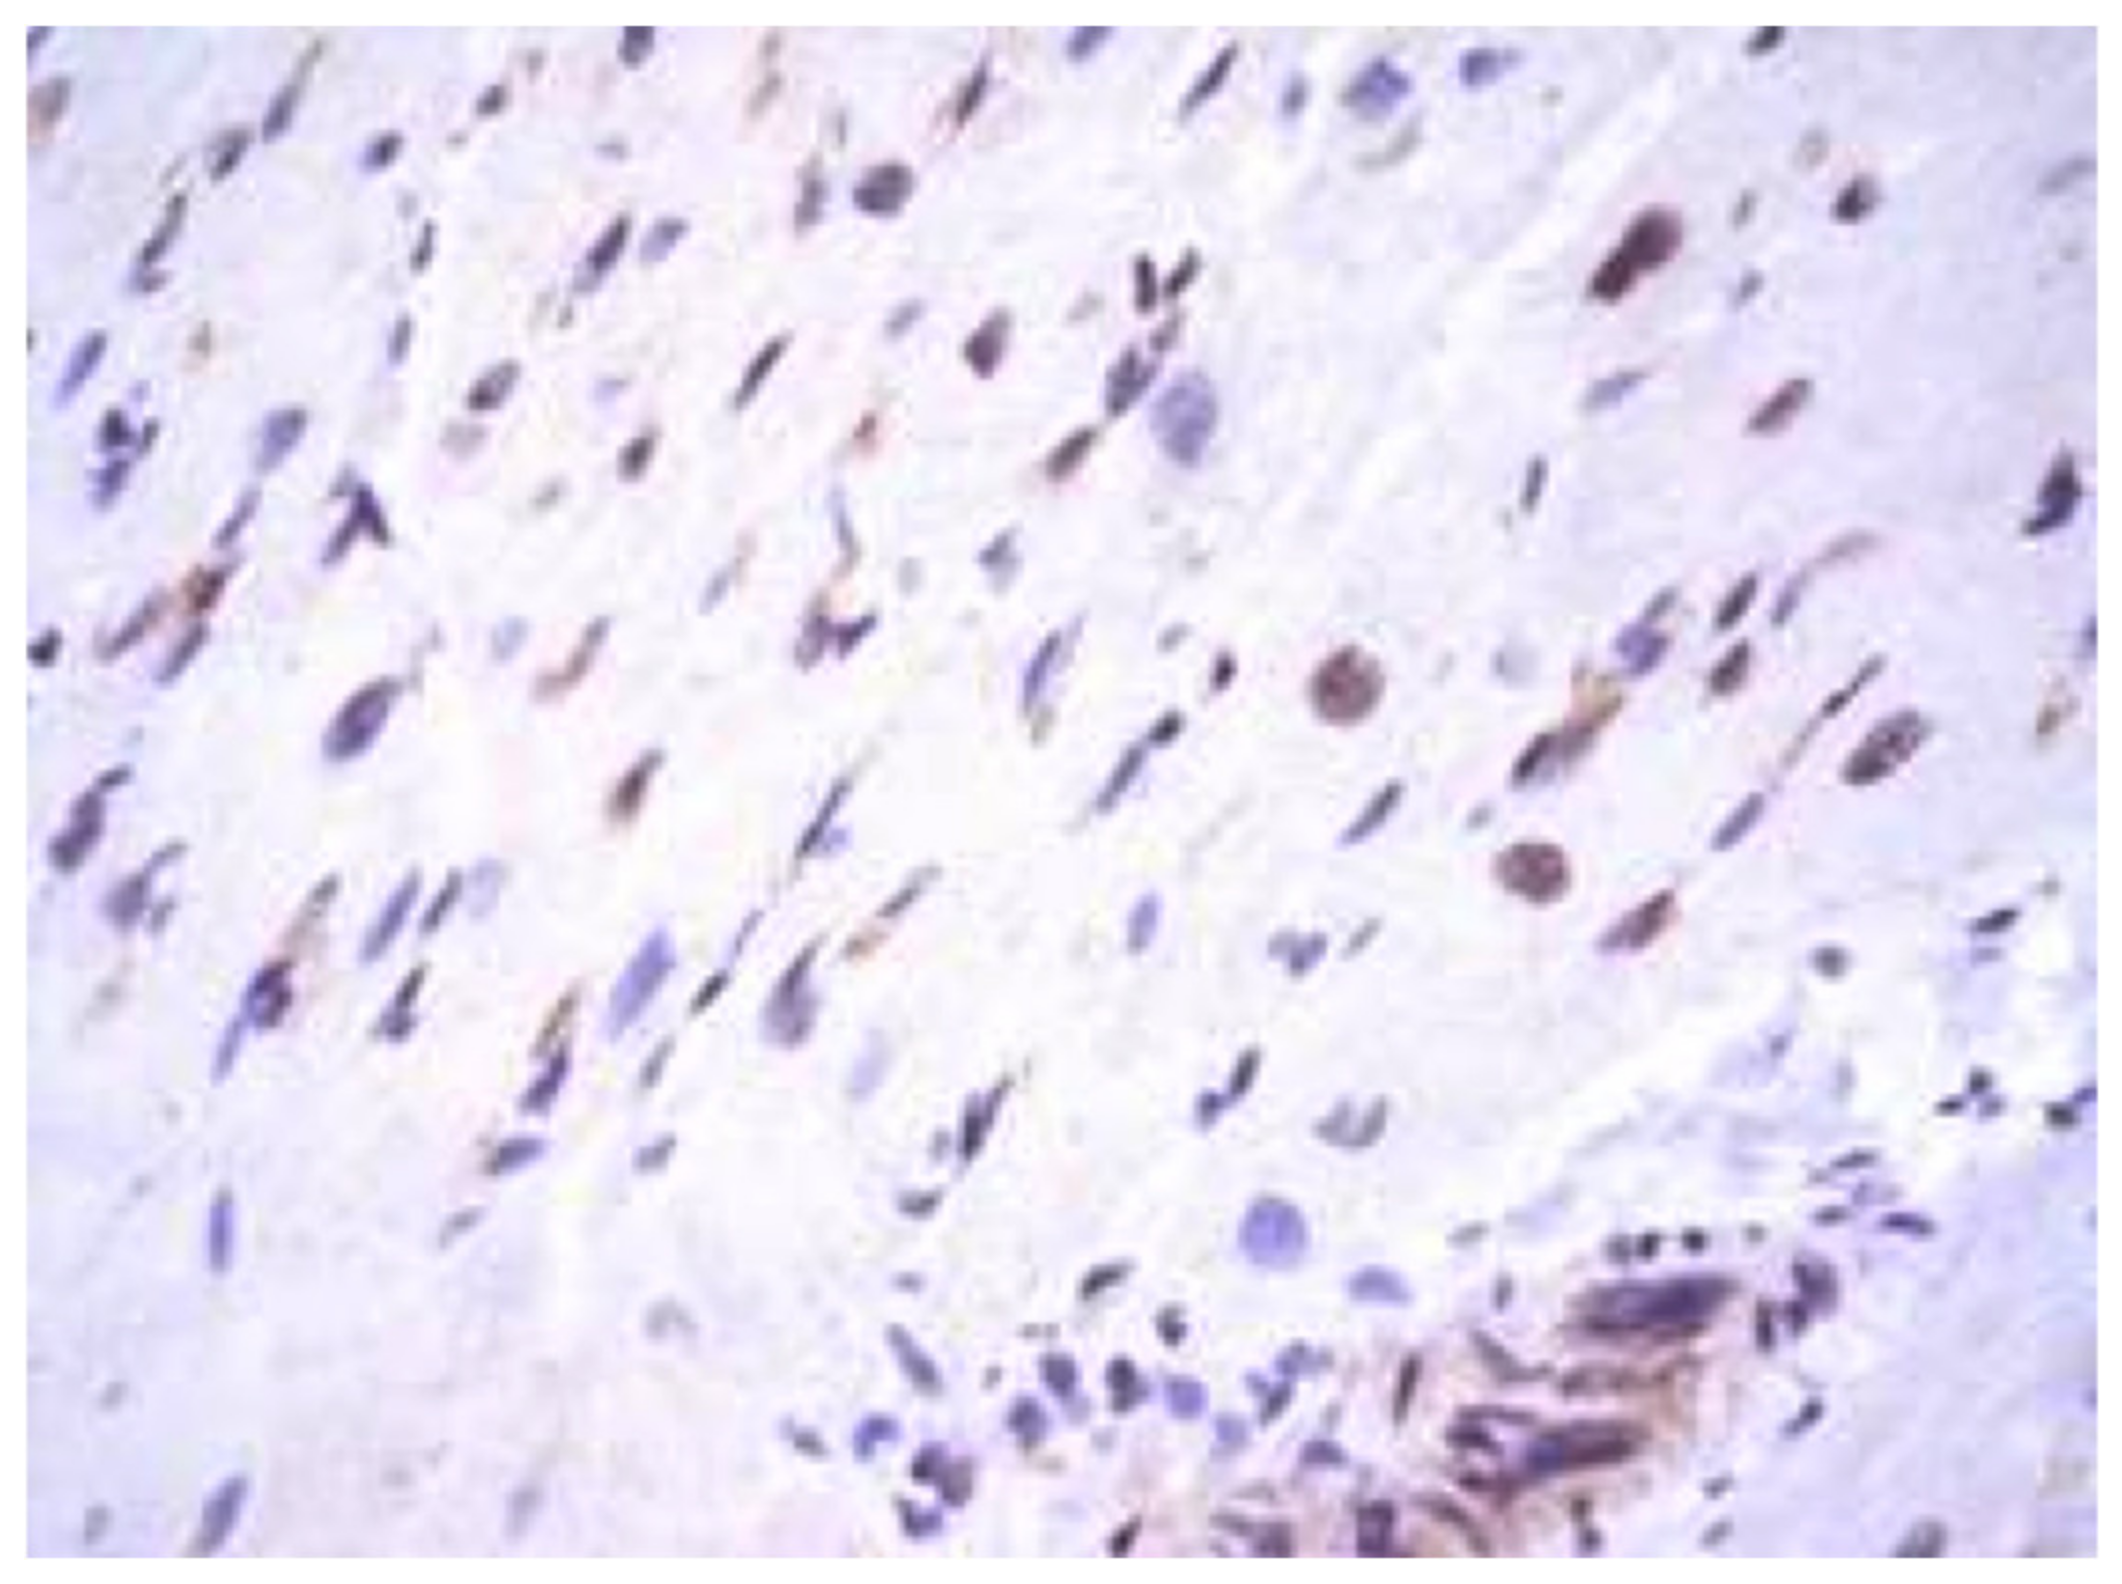

During generalized viral infection, herpes simplex viruses (the Herpesviridae family) often infect epithelial and endothelial cells, fibroblasts, smooth muscle cells, nerve cells, and macrophages, altering their antigenic and functional properties, as well as stimulating host immune response [41]. Such viruses in myocarditis are more often detected in fibroblasts and vascular endotheliocytes, with fewer found in cardiomyocytes (Figure 2).

Figure 2. Expression of antigens of herpes simplex virus type 2 (brown staining) in non-parenchymal myocardial cells in generalized intrauterine herpes virus infection. IHH, rabbit polyclonal anti-HSV-2 (BioGenex, Fremont, CA, USA), DAB. SW. ×200.